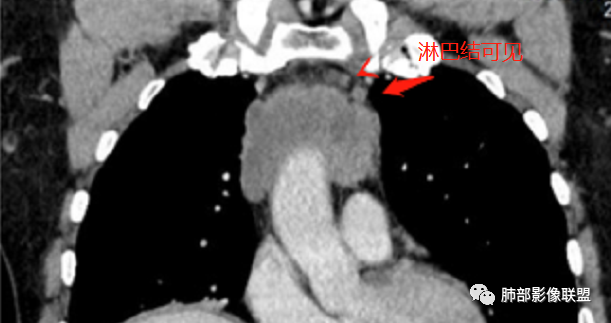

前纵隔胸腺区分叶状软组织肿块影,轻度不均匀强化,中心可见坏死,边缘不清,病灶与邻近心包见条索影,上腔静脉受侵,上纵隔多发小淋巴结,考虑胸腺鳞癌可能。

男性患者,65岁,前胸后背疼痛一个月。胸部影像:前上纵隔分叶状的软组织肿块,形态不规则,包绕大血管生长趋势,与周围分界不清,密度较均匀,呈多结节融合,肿块周围可见肿大淋巴结,内乳动脉旁淋巴结大,上腔受累,肿物内可见低密度区,增强扫描周围轻度强化。考虑:恶性病变,淋巴瘤?胸腺神经内分泌肿瘤?鉴别胸腺瘤

毛勤香:

老年男性,前纵隔肿块,形态不规则,右侧内乳动脉增粗,与血管脂肪间隙模糊消失,定性恶性,周围多发小淋巴结,有斑点状钙化灶,增强中心低密度区无强化,边缘强化为主,首先考虑胸腺鳞癌,鉴别胸腺瘤。

我记得黄勇老师的课件提到:内乳淋巴结、钙化有价值。

中老年男性,前纵隔占位,基本居中,向两侧生长;边缘膨隆分叶,部分边界不清,增强不均匀轻中度强化,坏死区边界不清;周围多发增大淋巴结,考虑恶性。主要在胸腺癌、胸腺瘤、淋巴瘤之间鉴别。病灶偏软,有钻缝样生长,这些征象偏向于淋巴瘤。但此例老年患者,病灶内有点状钙化,缺乏结节堆砌感,倾向胸腺癌诊断。